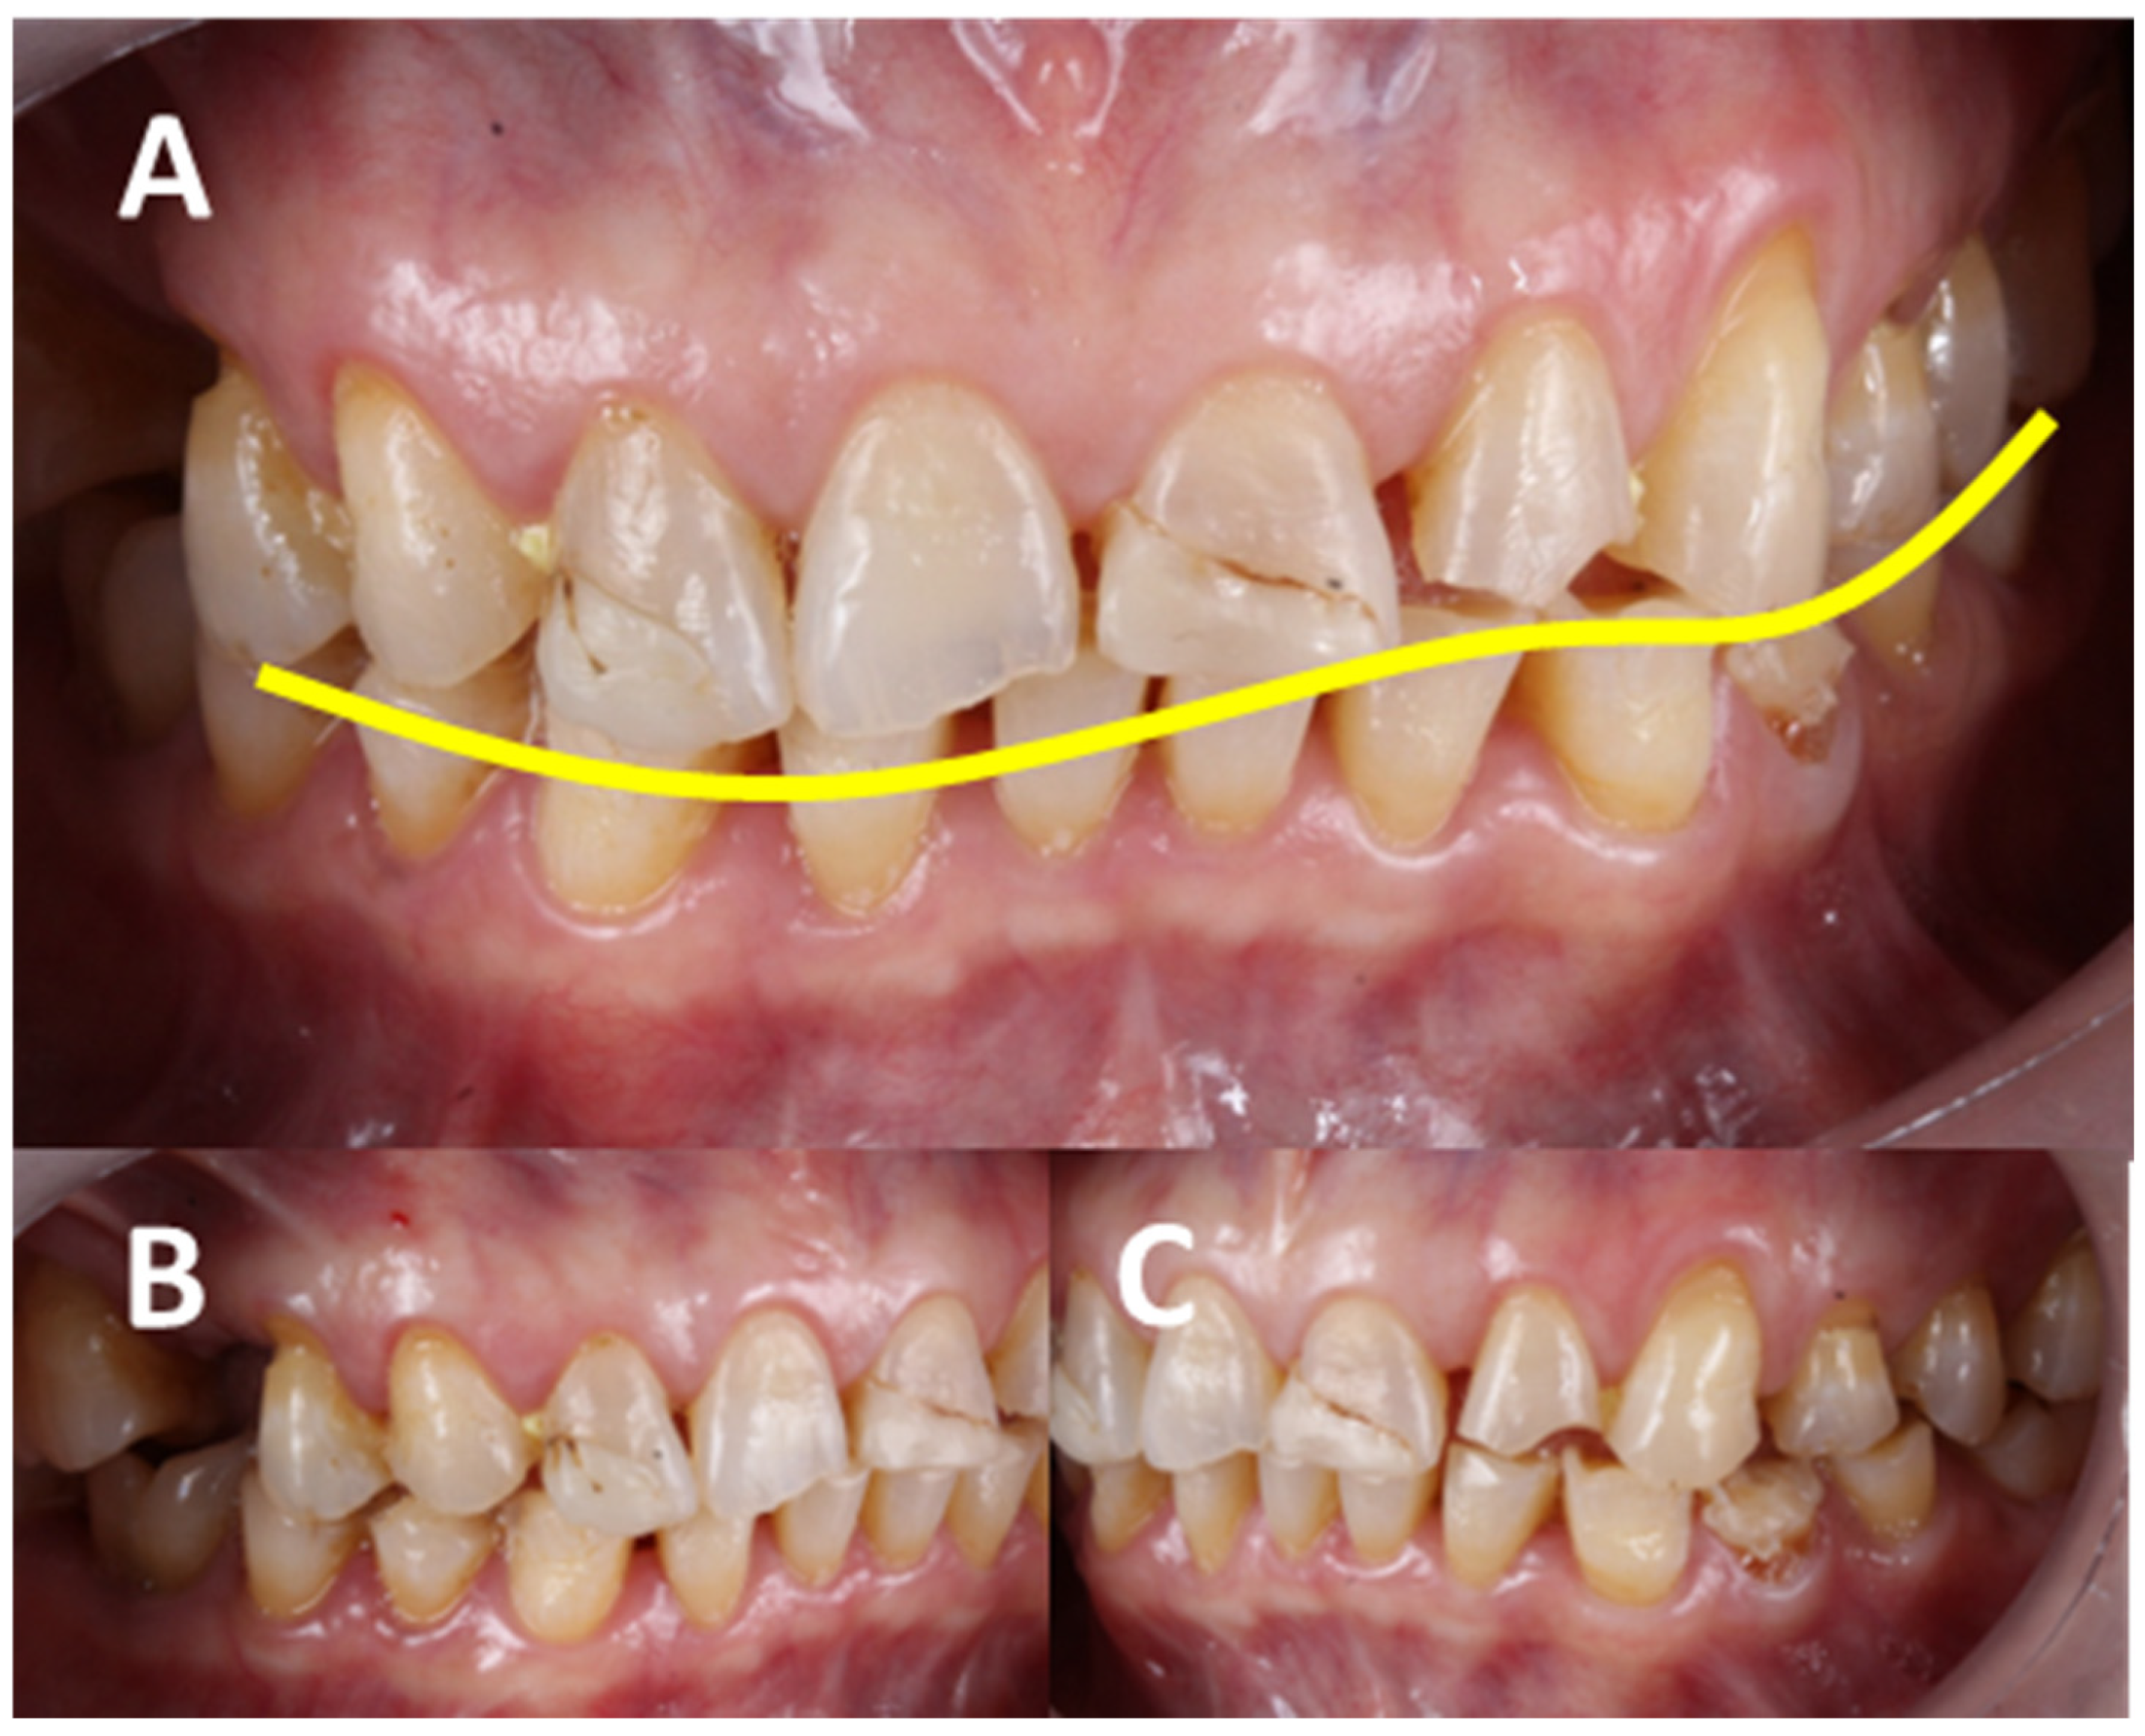

3.3.4. Dental-Level Influences